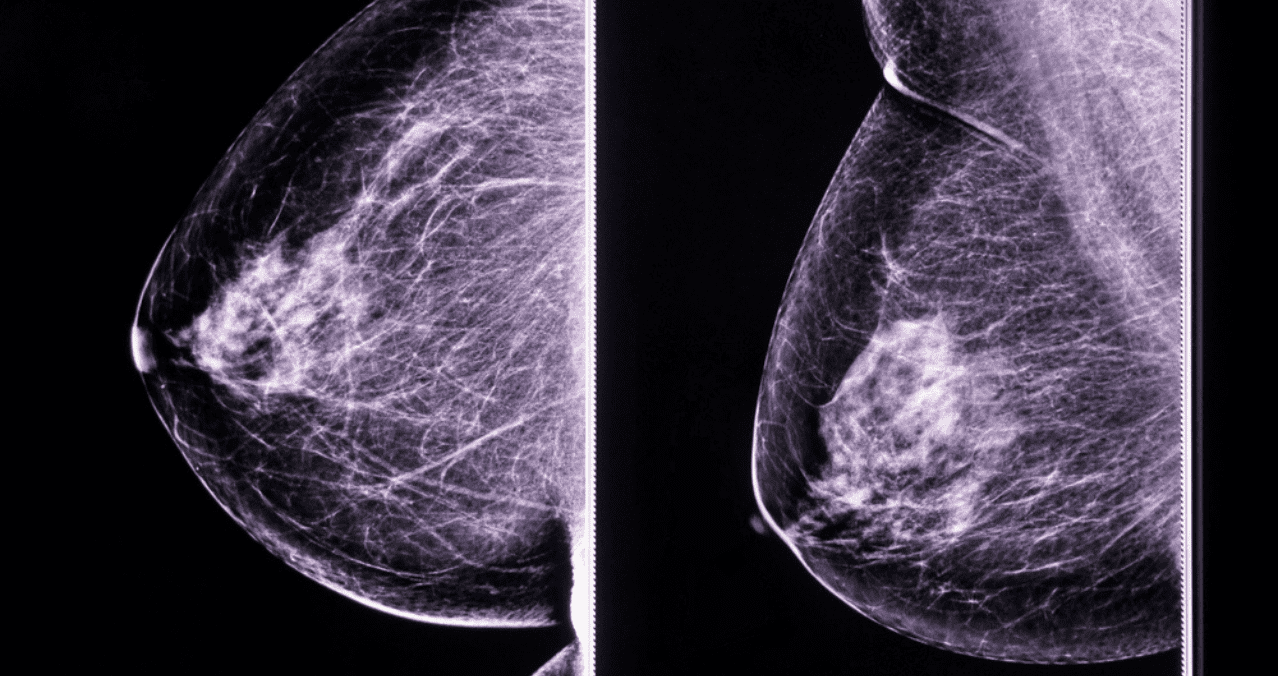

Este año, en el municipio de León se han efectuado 17,654 exploraciones clínicas de mama en mujeres mayores de 25 años en las unidades médicas jurisdiccionales, informó el secretario de Salud, Gabriel Cortés Alcalá. Asimismo, se realizaron 6,060 mastografías en el Hospital General de León y el Materno Infantil para detectar alteraciones sospechosas en etapas tempranas.

De esas acciones, 229 mujeres presentaron hallazgos sospechosos de malignidad clasificación BIRADS 4 y 5 y 52 casos fueron confirmados por la Secretaría de Salud local como cáncer de mama. La edad promedio de las pacientes es de 53 años, con un rango que va de 36 a 88 años.